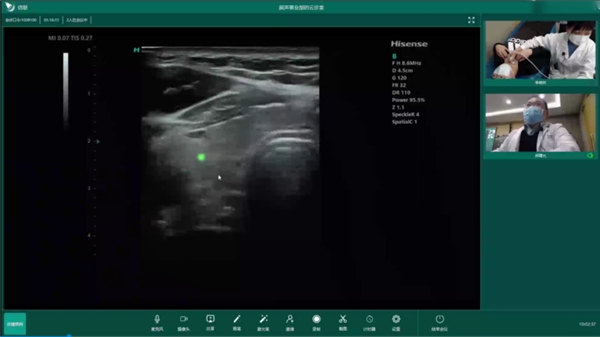

在遠(yuǎn)程超聲方面,海信醫(yī)療自研信聯(lián)遠(yuǎn)程超聲診斷系統(tǒng),采用現(xiàn)代通訊、電子和多媒體計(jì)算機(jī)技術(shù),實(shí)現(xiàn)了超聲遠(yuǎn)程實(shí)時(shí)診斷、遠(yuǎn)程教學(xué)、在線質(zhì)控和交流。前不久,在青島,超聲專家與遠(yuǎn)在1600多公里之外的定西市通渭縣平襄社區(qū)衛(wèi)生服務(wù)中心進(jìn)行了遠(yuǎn)程超聲會(huì)診,基層超聲醫(yī)生使用海信超聲為患者進(jìn)行超聲檢查,遠(yuǎn)端專家在線實(shí)時(shí)進(jìn)行操作指導(dǎo)和病例會(huì)診,會(huì)診大屏同步顯示清晰動(dòng)態(tài)的超聲圖像。會(huì)診過(guò)程中,聲音和畫面均做到了同步無(wú)延時(shí),遠(yuǎn)程超聲讓基層醫(yī)生和遠(yuǎn)端專家感受到身臨其境的會(huì)診體驗(yàn)。

海信遠(yuǎn)程超聲將上級(jí)優(yōu)質(zhì)專家資源下沉到基層衛(wèi)生院,專家通過(guò)遠(yuǎn)程會(huì)診的方式實(shí)時(shí)指導(dǎo)基層超聲醫(yī)師,實(shí)現(xiàn)基層疑難疾病的及時(shí)診療,提升基層醫(yī)生的檢查和診斷能力。憑借超聲產(chǎn)品和平臺(tái)優(yōu)勢(shì),海信遠(yuǎn)程超聲已經(jīng)在青島市以及山東省、珠海市、定西市等全國(guó)各級(jí)醫(yī)院以及體檢中心有了較為廣泛的應(yīng)用,實(shí)現(xiàn)患者就近就醫(yī)。同時(shí),海信醫(yī)療還牽頭編制了首個(gè)遠(yuǎn)程超聲團(tuán)體標(biāo)準(zhǔn),填補(bǔ)了該領(lǐng)域的行業(yè)空白,對(duì)于遠(yuǎn)程超聲診斷工作的開展具有積極的指導(dǎo)意義。